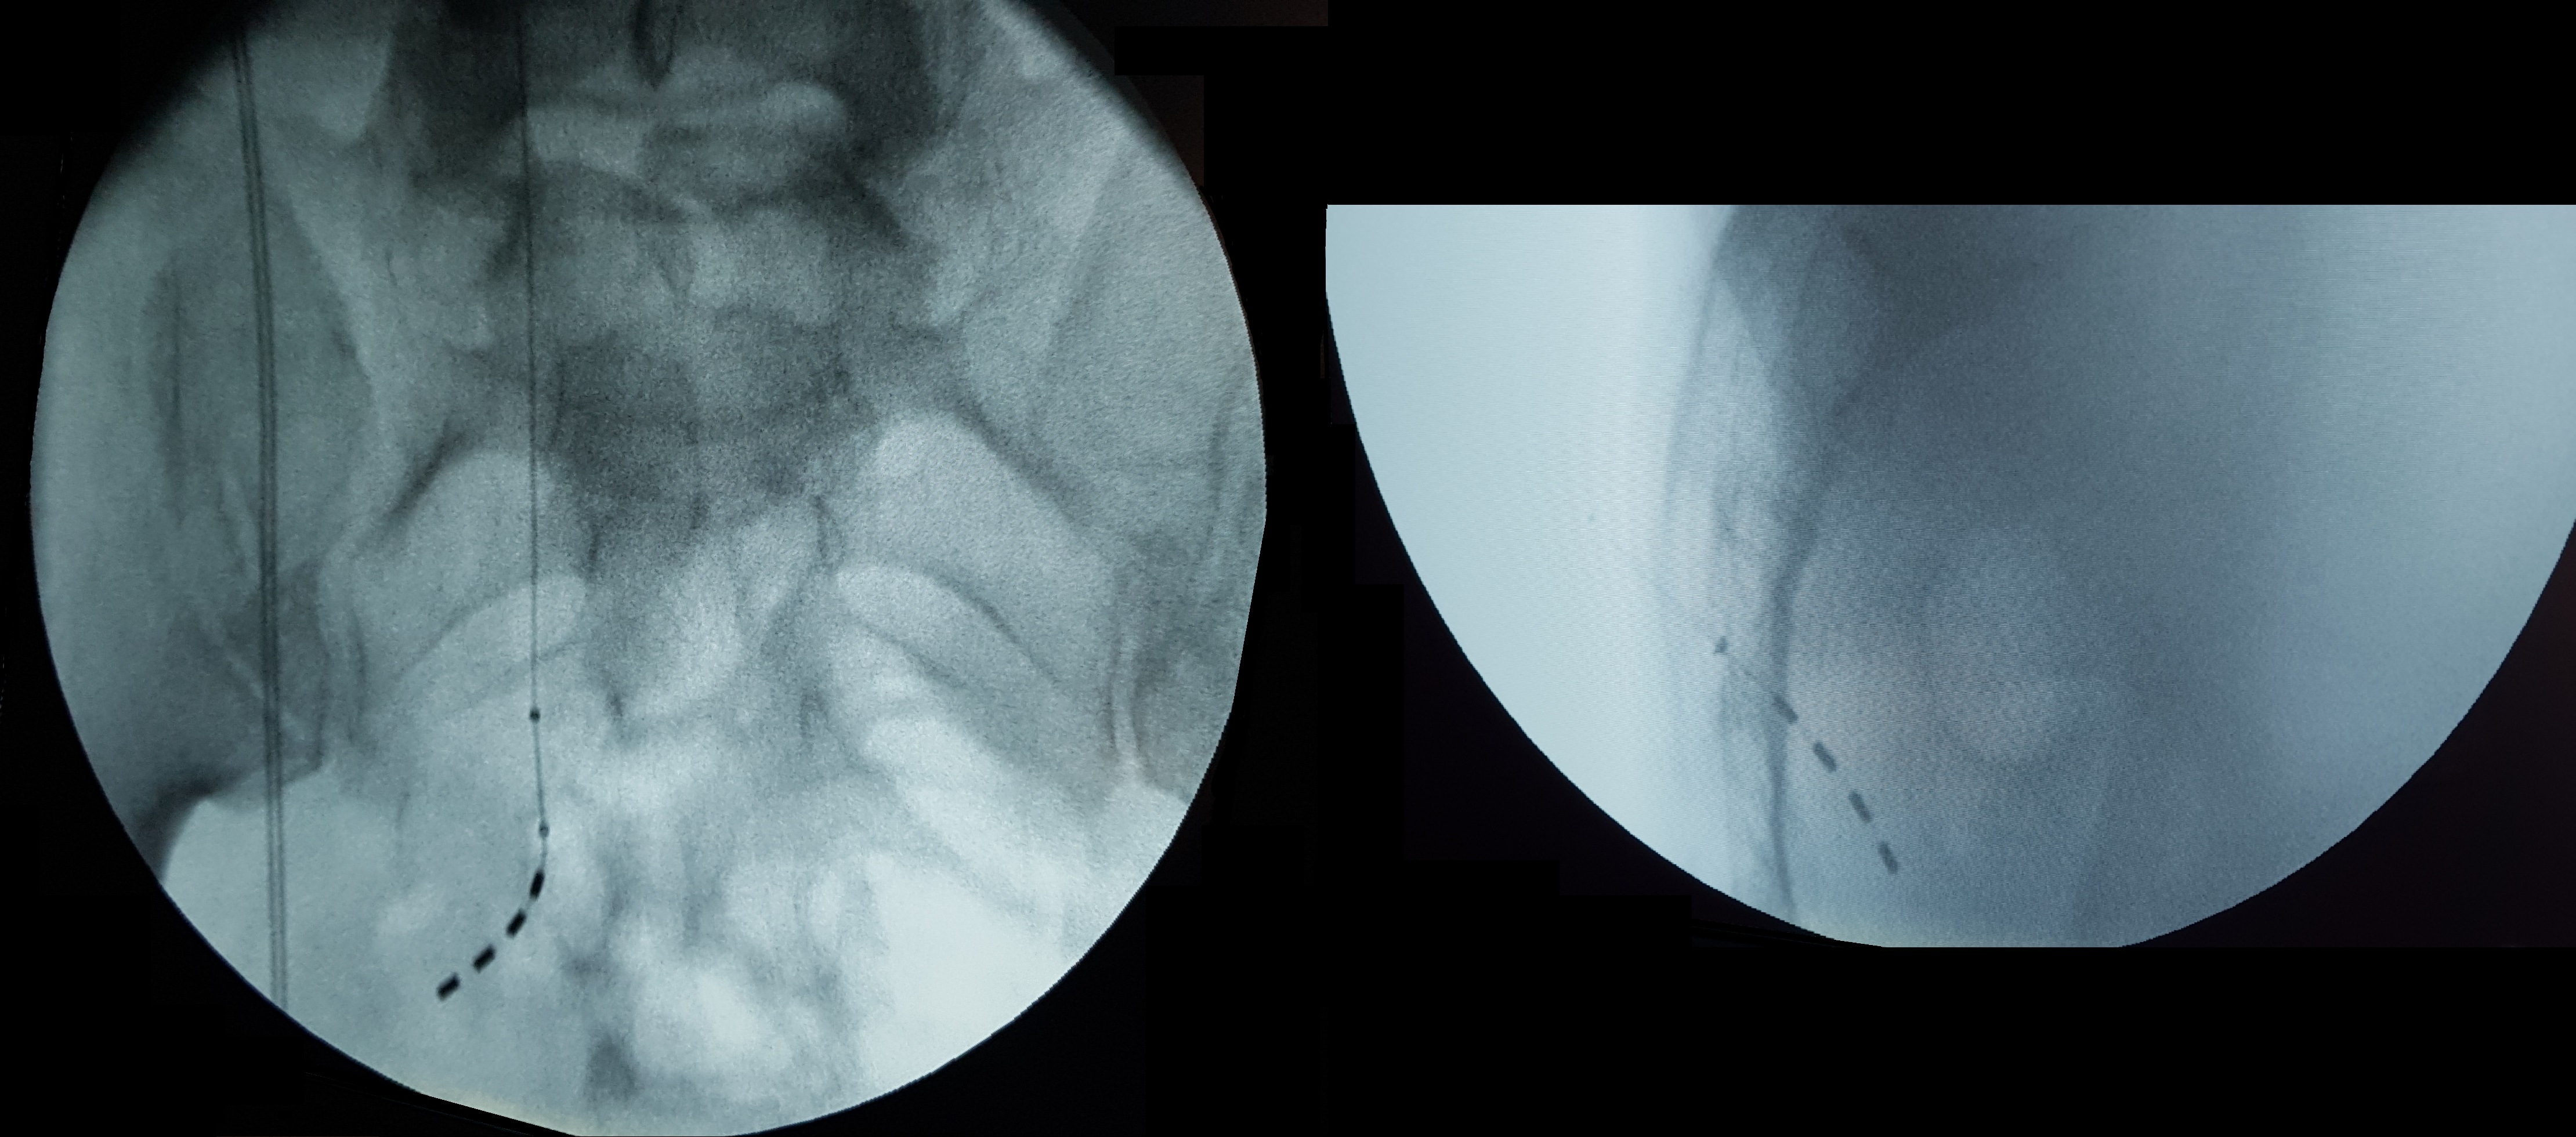

Во всех трёх наблюдениях имплантация электрода для SNRS с применением AR-навигации была выполнена успешно. Используя визуализированную траекторию (рис. 4) и корректируя направление иглы при малейших отклонениях от намеченного пути, удавалось без затруднений выйти на область крестцового отверстия S3 с медиальной стороны и затем выполнить правильное размещение электрода. Точность позиционирования подтверждалась финальным рентгенологическим контролем в завершении вмешательства (рисунок 5).

Рисунок 5. Рентгенологический контроль расположения электрода в S3 отверстии справа.

При выполнении данной операции применение навигации с дополненной реальностью оказалось даже более результативным. Точное следование заранее рассчитанной траектории введения инструмента (рис. 6) обеспечило оптимальное расположение электрода в крылонёбной ямке, что впоследствии сопровождалось выраженным положительным клиническим результатом. Корректность положения стимуляционной иглы была подтверждена интраоперационной флюороскопией, после чего произведена имплантация четырёхконтактного электрода. Финальная позиция системы была дополнительно верифицирована по данным послеоперационной компьютерной томографии (рисунок 7).

Поскольку рентгенологический контроль в данном случае был ограничен выполнением нескольких статических снимков в прямой и боковой проекциях, он использовался исключительно для подтверждения окончательной позиции электрода. Суммарное время флюороскопии составило 0,1 ± 0,1 мин, а средняя эффективная доза облучения — 0,7 ± 0,5 мЗв. Эти показатели значительно ниже типичных значений для аналогичных вмешательств, особенно при сложных клинических условиях, когда длительность флюороскопии может достигать нескольких минут [8,9].